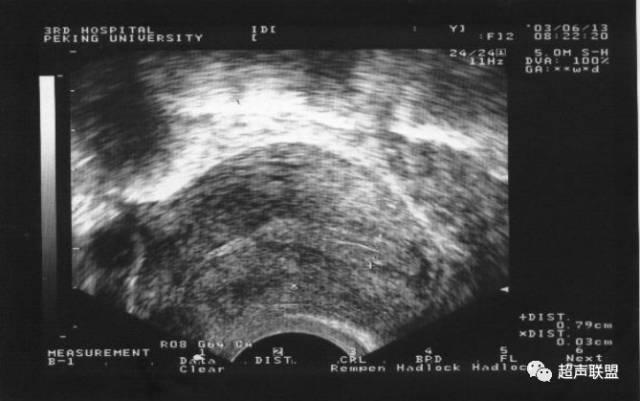

卵泡破裂24小時

黃體期

促排卵周期的患者,為確保排卵、更好地把握受孕時間、同時增強黃體功能,常規用人絨毛膜促性腺激素(HCG)注射誘發排卵,指導患者夫婦受孕。HCG注射後48小時複查超聲波,如成熟卵泡已消失或塌陷,則可適當給予孕酮進行黃體支持10~14天。